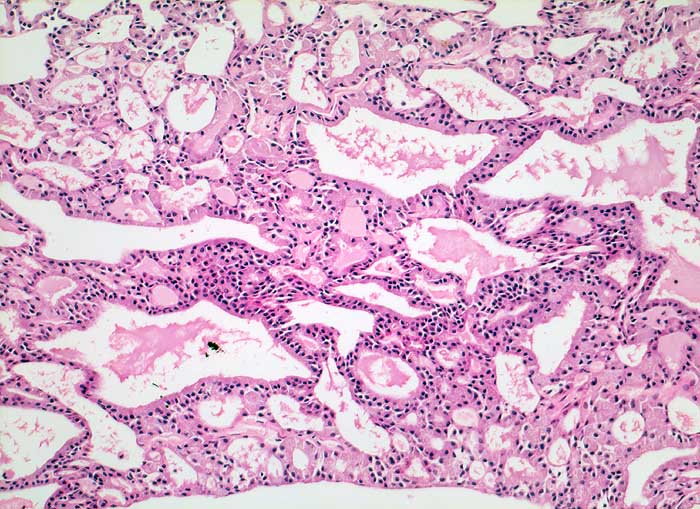

Azinuszellkarzinom

maligner Tumor

Parotis

An Schilddrüsenparenchym erinnerndes follikuläres Wachstumsmuster. Hochprismatische Tumorzellen mit kleinen Kernen und reichlich hellem Zytoplasma.

Histologie

100